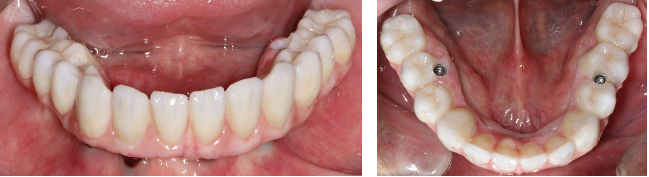

Implant-Retained and Implant-Supported Removable Prostheses

An implant-retained and implant-supported removable prosthesis may be fabricated by using a bar or a conical, titanium abutment with a 5-degree taper (Figure 18).49 In the next case, a fixture-level impression was made and records were registered and sent to the laboratory with the abutments (preselected based on the height of the mucosal cuff) for framework and prosthesis fabrication.49 The prosthesis had recesses on its intaglio surface to permit pickup of the abutment caps (Figure 19).49 The abutments were attached to the implants in the mouth (Figure 20). A jig/index provided by the laboratory (Figure 21) was used to seat the abutments intraorally so that they were positioned exactly as they were on the master cast. Gold caps were placed over the abutments and were picked up in the prosthesis intraorally (Figure 22).49 (Gold caps that fit over the abutments provide excellent retention, which improves over time.)50 The prosthesis was adjusted, finished, polished, and placed in the mouth (Figure 23). The prosthesis was entirely supported by the implant abutments.49 It had excellent retention and stability (almost like a fixed restoration) because it was entirely implant-supported; yet, it was removable.49